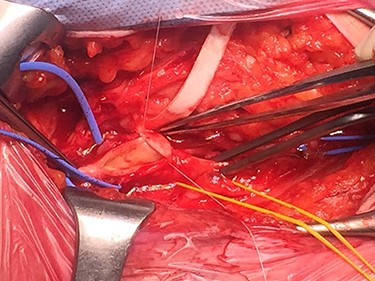

During surgical dissection of the right groin and isolation of the CFA, a jelly-like lesion of the anterior wall of the CFA was detected. The lesion caused a compression of the arterial lumen and determined its critical stenosis, with subsequent peripheral hypoperfusion leading to intermittent claudication. An accurate excision of the cystic material was performed and the clear gelatinous material leaked was collected along with a specimen of arterial wall for cytological and histological examination (Fig. 3). The surgical procedure was then completed with excision of the unhealthy arterial wall of the CFA and placement of a polyurethane patch.

The intraoperative completion DUS showed the patency of the CFA and of the femoro-popliteal axis with triphasic flow maintained until tibial vessels (Fig. 4).